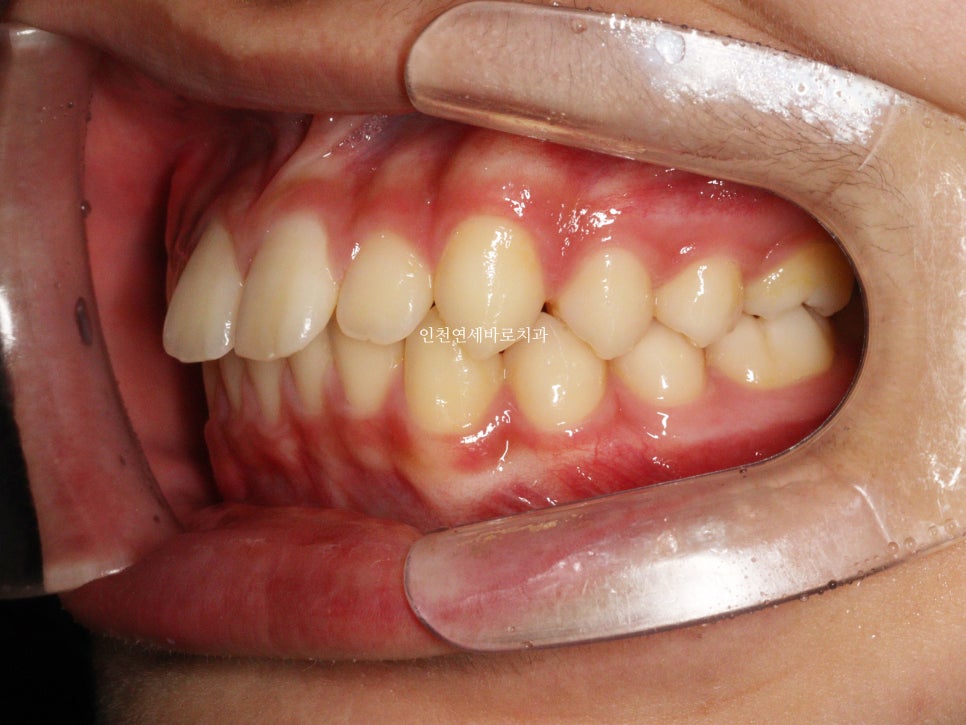

치료 전과 후 입니다.

앞니가 후방이동 한것이 확인됩니다.

전과 후의 얼굴 변화입니다.

치아가 들어가보입니다.

앞니만 철사를 붙여서는 얻기 어려운 결과라고 생각합니다.